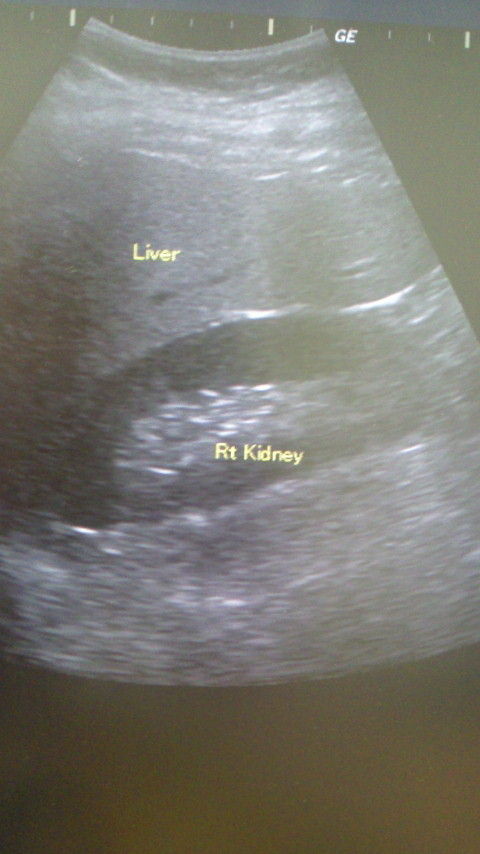

最後にお話を聞いた、超音波の結果は、『少々、脂肪肝気味ですねぇ・・・』と先生。